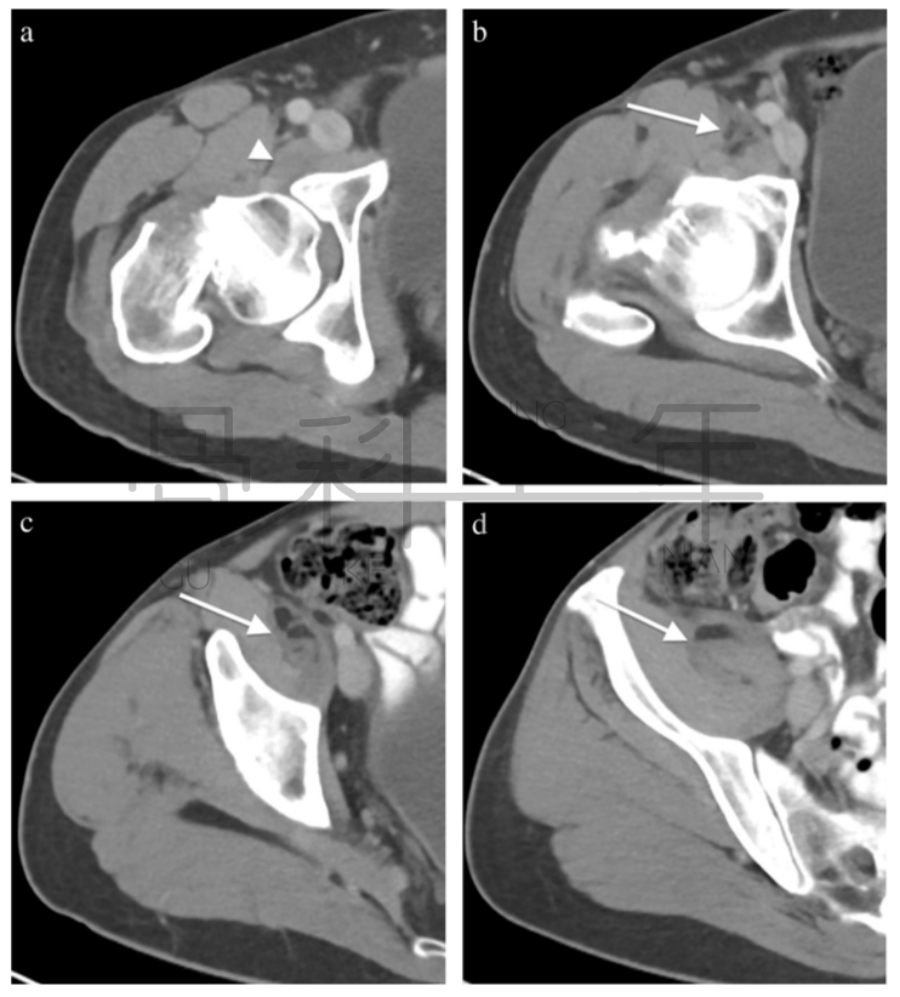

病例4股骨颈骨折,在CT横断面骨窗上未见明显液体分层(a),在软组织窗(b)可见高密度血肿影(箭头所示,CT值为50HU)。